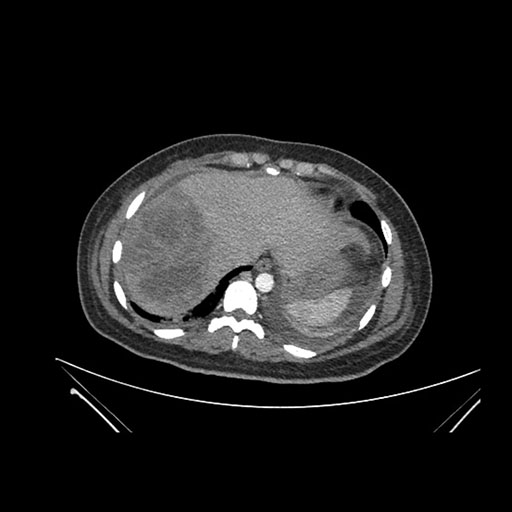

Coronal Venous